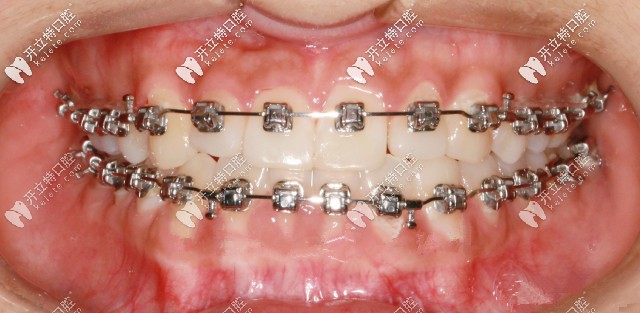

先戴頜墊再做矯正

此案例是戴頜墊3個(gè)月左右,解除反頜后開在粘接托槽